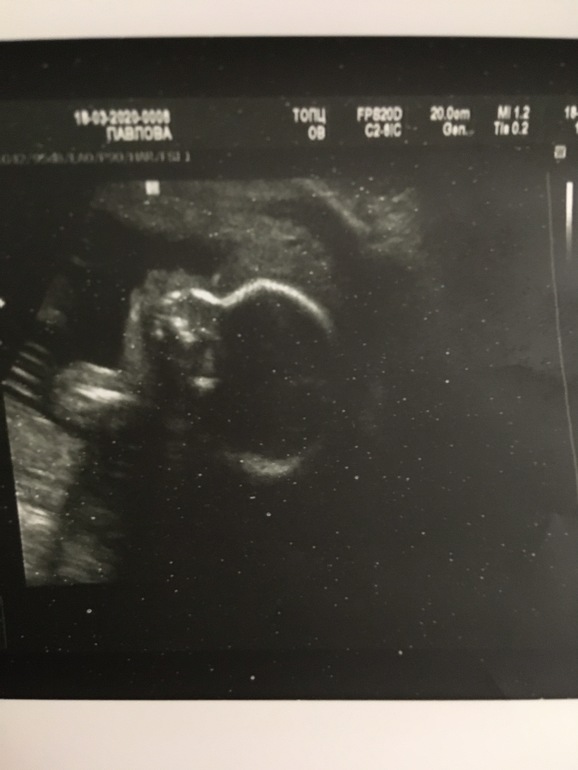

Ничего не болит и не беспокоит, кроме не дышащего носа по ночам, но тут только терпеть. Высота матки 27см крупная девочка 🥰, давление 100/60. Шевеления ощущаю хорошо в основном утром и вечером перед сном! Как день затишья, я сразу за доплер! Все точно так же как и в прошлую Б, завтра сдавать гтт думаю поставят опять диабет тк дома на глюкометре натощак 5,7 сахар - печаль! Ну и фото малышки на 22 нед и мои.